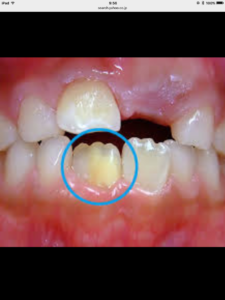

ホワイトスポット(白濁)と少し似たように見えますが、

エナメル質形成不全とは、

エナメル質が作られる時期に何らかの原因によってエナメル質がうまく形成されなかった歯の事です。

好発部位は

上の前歯や様々ですが、左右対称に出来る事もあります。